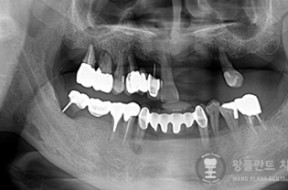

전후사례